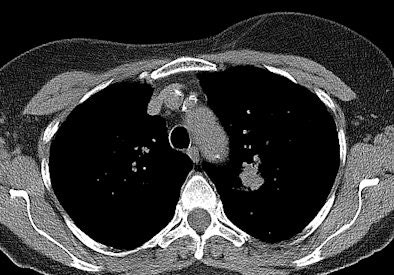

The NLST has shown that lung cancer death rates can be reduced by 20% when a high-risk group is screened with a low-dose CT scan compared with chest radiography. The participants were asymptomatic persons ages 55 to 74 who had smoked at least 30 pack years in their lifetime. Participants received a baseline CT scan and two annual screening CT exams, and were then followed for a median of 6.5 years. Screening of high-risk individuals led to a better opportunity for curative treatment, the investigators found.

"There are many potential advantages of CT screening," Heuvers pointed out. "Low-dose CT is not only a valuable tool to detect lung cancer at earlier stages, it can also be used to monitor other causes of morbidity and mortality in heavy smokers, such as ischemic heart disease and chronic obstructive lung disease (COPD). Early detection of coronary artery calcification could be used to identify patients who are likely to experience ischemic heart disease. In addition, early detection of COPD could signify patients with a rapid progression of their COPD, leading to an intensive treatment."

Screening for other causes of morbidity and mortality in heavy smokers might increase the cost-effectiveness of screening programs, especially if positioned in multidisciplinary programs that provide smoking-cessation programs. CT scans can play an important role in research to understand the etiology and pathophysiology of COPD, she added.